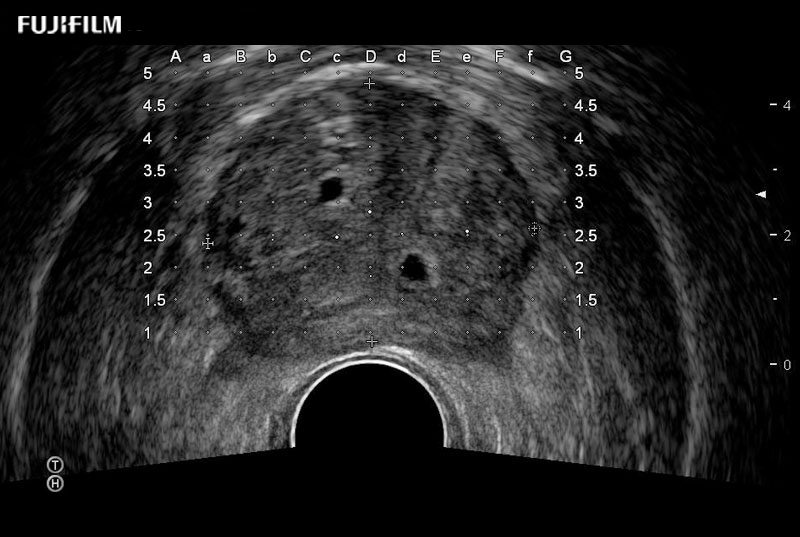

Exclusive 200° FOV end-fire prostate biopsy transducer.

Main Specifications:

Provides real-time imaging of both the sagittal and transverse planes